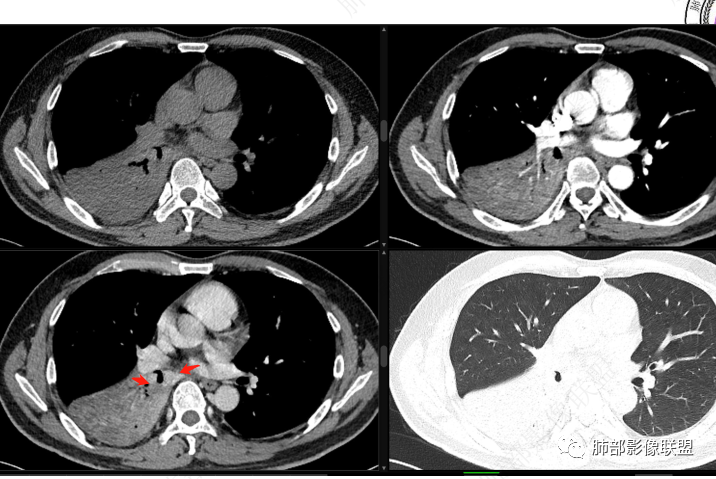

右下叶支气管狹窄,内见高密度强化结节,远端大片不张实变,实变内可见多发粘液拴,整体观察实变似有见缝就针的感觉,综和分析考虑粘液表皮样癌,其次考虑类癌

中央型肿瘤pk周围型肿瘤  。壮年男性,热咳一周伴气喘,中性白细胞升高,临床是个感染过程。支持中央型病变的证据:1  肺门明显强化结节 2 横s征  3 支气管粘液栓  4 主支气管变窄,似见冰山征      支持周围型病变:1 按叶段塑形  2 血管造影征  3 病灶内弥漫高强化  4 周围伴磨玻璃灶,但境界不清继发感染?误吸?综合 中央型肿瘤可能大:类癌》鳞癌

右肺下叶不张,右下肺门区高强化结节,似乎呈冰山征,首先考虑类癌可能

位移:

右下肺门似见一结节影,明显强化,远端支气管黏液栓,右肺下叶不张,考虑类癌,次之黏液表皮样癌 腺样囊腺癌

右肺下叶支气管见结节灶继发右肺下叶膨胀不全,右肺中央局部炎性改变,下叶支气管结节动脉期明星强化,静脉期强化减低,首先考虑肺鳞癌,鉴别类癌、粘液表皮样癌。

首先血管未见明显侵犯、移位,提示病灶:炎性;肿瘤:外朝内——含粘液类腺癌(肺门淋巴结转移),腔内肿瘤(鳞癌、腺癌、类癌、小细胞、粘液表皮等)

从强化看:外周密度低,强化弱

就不太符合腔内肿瘤远端不张的表现,因为外围不张——强化明显

腔内肿瘤,远端堵塞